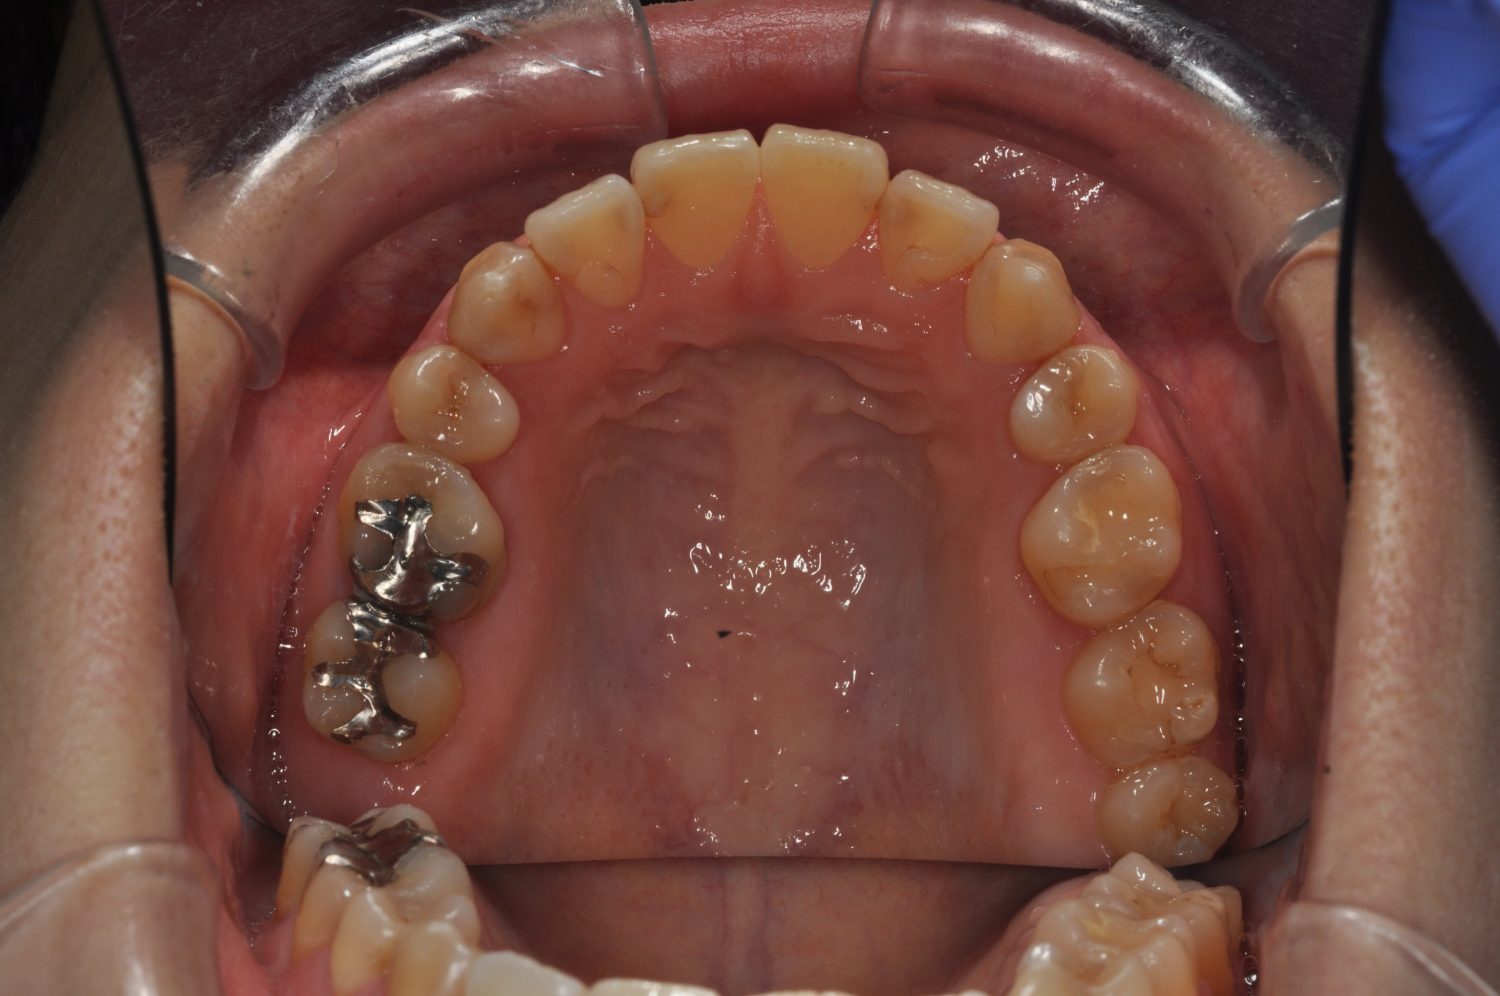

| 主訴 | 口上下顎のガチャガチャが気になる |

| 治療内容 | 歯冠幅径が大きいことから、IPRを併用した非抜歯治療 |

| 治療費 | Ⅱ期治療費:247,500円(税込) 調整料 5500円(税込)×11回 保定時:22,000円(税込) 計 330,000円(税込) |

| 治療期間 | 1年2ヶ月 |

| 治療回数 | 13回 |

| 想定されたリスク | 矯正中の清掃状況によってはむし歯や歯周病のリスクがありました。歯根吸収や歯肉退縮のリスクもありました。 |

Ⅰ期治療で前歯部反対咬合をセクショナルアーチとMPAを使用して改善した後、成長観察を行っていました。永久歯が萌出したため、Ⅱ期治療を開始することとなった。上下顎とも骨格的に問題がなかったため、非抜歯で治療を行った。